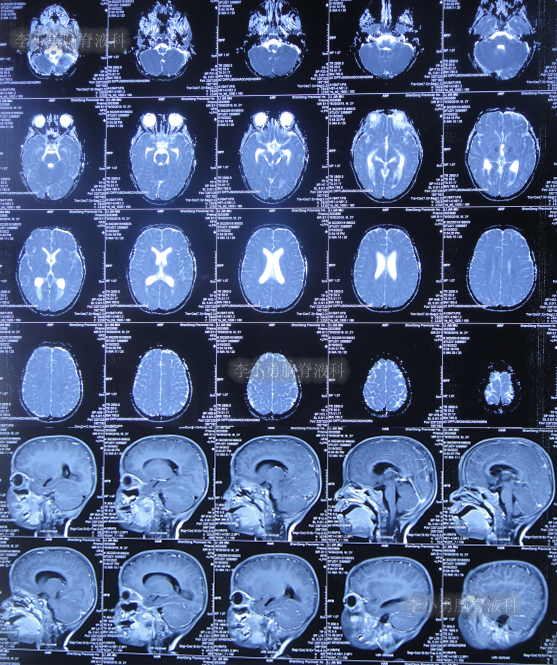

住院治疗7天即2022年5月18日,出现头痛,呕吐,体温再次升高为39.6度,心电图示室性心动过速,室早,考虑“心肌炎”,查头颅核磁(图-1)后并行腰穿见脑脊液呈金黄色,留取脑脊液送常规化验提示诊断为颅内感染,给予抗感染治疗。

图-1:2022年5月18日头颅核磁